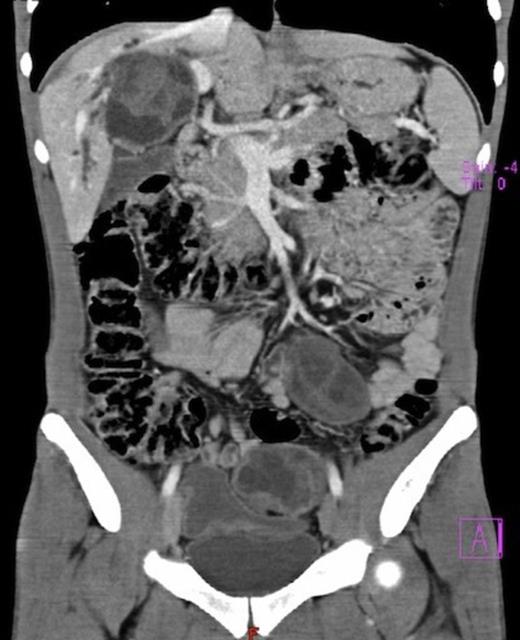

Surgical exploration confirmed the numerous peritoneal hydatid cysts and identified more lesions in the larger omentum (ranging from 3-12 cm) (Fig. 3). They were all resected, and a splenectomy was performed to remove completely the hilum cyst (Fig.4). Hydatid disease of the liver was massive, except in segments 1, 2 and 3. A cyst developing in segment 7 (7 cm) invaded the diaphragm and another voluminous cyst of 12 cm occupied the entire segment 8. A cyst of 8 cm in segments 4 and 5 involved the hepatic confluence, with destruction of the right hepatic duct and promoting a major biliary fistula with the left hepatic duct, confirmed by intra-operative transcystic cholangiography. The left hepatic duct near the hilar plate was included in the pericystic wall near segment 3. This cyst was chemically inactivated using iodopovidone (20 minutes), evacuated and followed by a thorough exploration of the cavity, which showed multiple biliary fistulae from the right sectorial hepatic ducts and a large defect in the left hepatic duct (Fig. 5). An extended right hepatectomy (segments 4 – 8), partial resection of the diaphragm and partial resection of the left hepatic duct including the fistula was performed. Reconstruction of biliary continuity was assured by a hepaticocholedocostomy, over a T-tube (Fig. 6). Confirmation of sectorial left hepatic ducts patency was done by intra-operative cholangiography.

Hepatic hydatid cyst in segments 4 and 5, after inactivation and evacuation, involving the hepatic confluence, with total destruction of the right hepatic duct and fistula formation to the left hepatic duct.